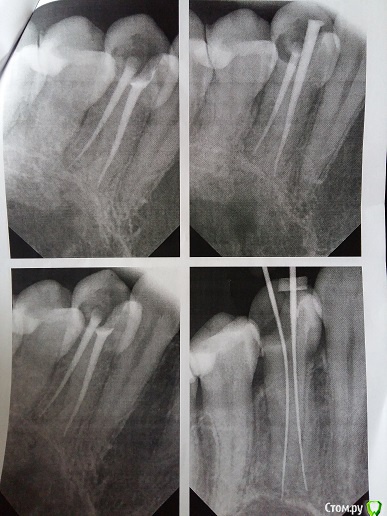

Kateklim Опубликовано 27 ноября, 2015 Автор Поделиться Опубликовано 27 ноября, 2015 Снимки, которые мне дали в частной клинике. Ссылка на комментарий

Гарриевич Опубликовано 27 ноября, 2015 Поделиться Опубликовано 27 ноября, 2015 по снимкам все адекватноесли использовали правильный протокол лечения, то результат будет хороший Ссылка на комментарий

IvanK Опубликовано 27 ноября, 2015 Поделиться Опубликовано 27 ноября, 2015 Хочу вернуть деньги в частной клинике. Думаю, что Вы торопитесь Лечение таких процессов почти везде без гарантии 2 Ссылка на комментарий